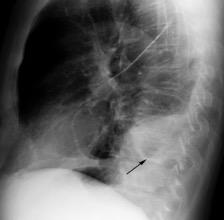

Marzo 2014: Perforación longitudinal distal secundaria a episodio de vómito (síndrome de Boerhaave). Derrame pleural izdo. que evoluciona a empiema.

Wang C-T et al. Tension hydropneumothorax in a Boerhaave syndrome patient: A case report . World J Emerg Med, 2021. Katabathina V et al. Nonvascular, nontraumatic mediastinal emergencies in adults:a comprehensive review of imaging findings. Radiographics. 2011.